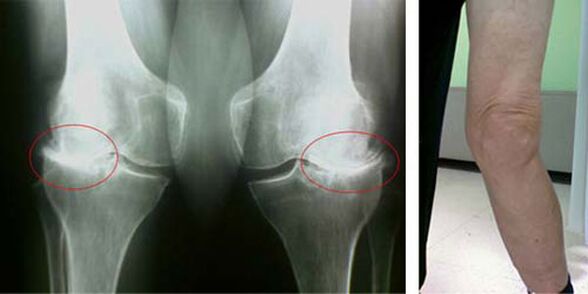

The initial stages of the occurrence of such a pathology as arthrosis of the knee joint do not manifest themselves visually at all. However, after a while, the patient notices signs of knee deformity, as well as a characteristic curvature along the axis of the leg (directed inward). There is also a crisis when you need to bend your leg.

The presence of pain, limited movement in the knee makes the person see a doctor and have an examination. To do this, he needs to undergo tests and take an x-ray of the diseased joint. If these measurements are not enough to confirm osteoarthritis of the knee joint, MRI is performed. Based on the data collected, the doctor chooses the best treatment methods.

knee osteoarthritis radiography